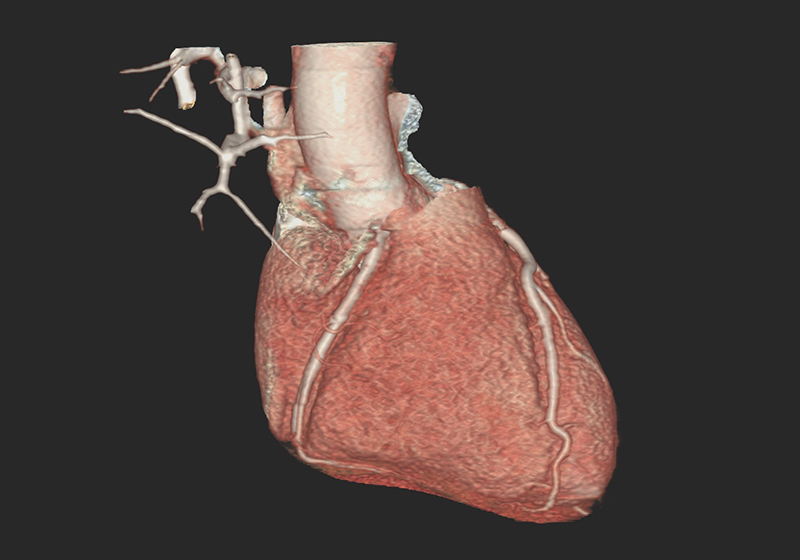

Über eine 3D-Nachverarbeitung werden die Herzkranzgefäße sowie eventuelle Engstellen und Verkalkungen dargestellt und vermessen. Sofern vorhanden, können an dieser Stelle auch Stents oder Bypässe auf deren Durchgängigkeit überprüft werden.